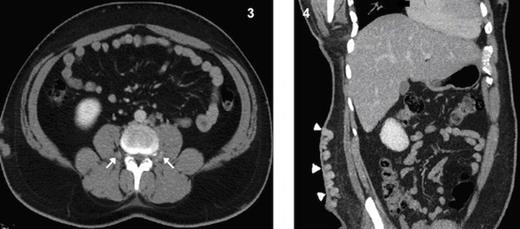

Coronal MPR CT image shows a long left renal vein seen draining into the intra-hepatic segment of IVC. Fig. 6 Coronal MPR CT image shows a right renal collateral vessel draining into hypoplastic segment of IVC.

The right renal vein is absent represented by long tortuous collateral draining into hypoplastic segment of IVC (Fig. 6) and multiple collaterals draining into the retroperitoneal venous plexus (Fig. 7). The right great saphenous vein exhibits drainage into the distal part of right common femoral vein (Fig. 8).